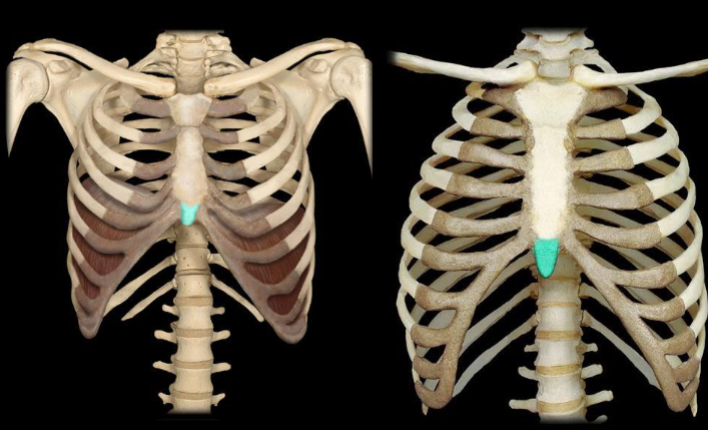

What part of the sternum is highlighted in this image?

xiphoid process (tip)

What bone is highlighted in this image?

costal cartilage (medial, touching the sternum)